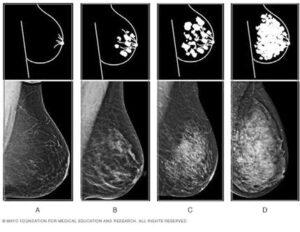

Densidad Mamaria

¿Qué es la DENSIDAD MAMARIA? Se refiere a como vemos el tejido de la mama en una mamografía. La mama está compuesta por dos tipos